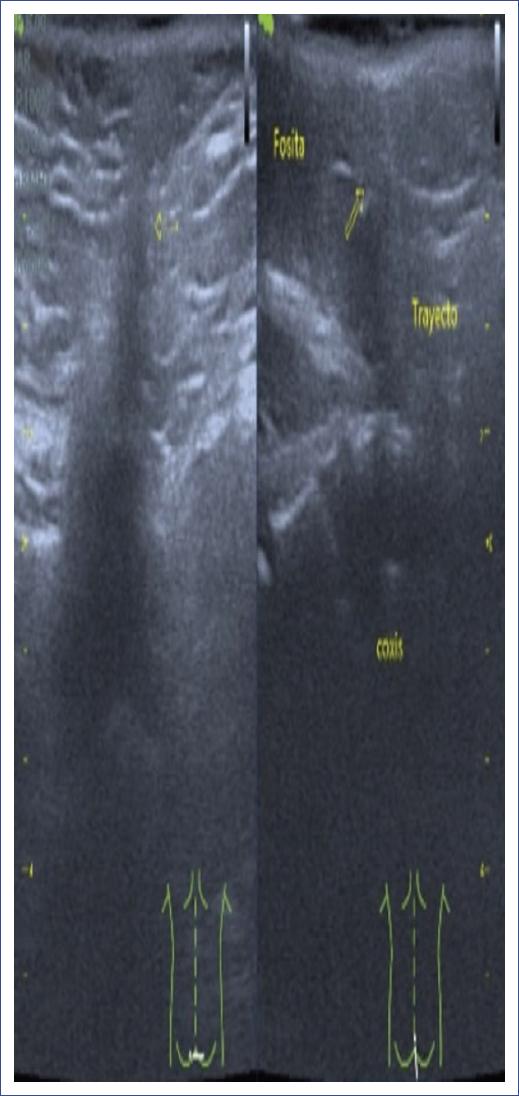

Por grupo etario pediátrico encontramos predominio de afección motora, disfunción vesical y estreñimiento en lactantes, preescolares y escolares; en cambio en los adolescentes y preadolescentes hubo predominio de lumbalgia. Se identificaron estigmas cutáneos en el 61.11% de los pacientes (n = 11), siendo una cola humana, dos hemangiomas en pacientes operados de mielomeningocele, cuatro lipomas subcutáneos y cuatro hoyuelos dérmicos en pacientes con seno dérmico. La figura 1 muestra imágenes representativas de los estigmas cutáneos identificados en nuestra serie. Para el diagnóstico por imagen se utilizó la RM lumbosacra en 17 casos y el US lumbosacro en dos casos, US transquirúrgico en un paciente con cola humana y US como tamizaje diagnóstico en un paciente con hoyuelo dérmico, fiebre y paraplejia, que sugirió un trayecto fistuloso y posteriormente se complementó con RM lumbosacra (Fig. 2). La RM confirmó el diagnóstico de anclaje medular en el 94.4% de los casos. En la figura 3 se ejemplifica la correlación de los hallazgos de anclaje medular por RM y los hallazgos transquirúrgicos en paciente con filum hipertrófico y megavejiga por disfunción vesical (paciente 14), paciente operado de mielomeningocele y adherencia medular a la duramadre (paciente 13), paciente con lipomielomeningocele y lipoma que penetra a la médula espinal (paciente 8) y paciente con seno dérmico, donde se aprecia un trayecto fibroso que atraviesa la vértebra (paciente 7).

Figura 2 Ultrasonido en paciente de 18 meses con hoyuelo dérmico, sugiriendo un trayecto fistuloso. Se complementó el diagnóstico con resonancia magnética, identificando un seno dérmico lumbosacro. Las flechas amarillas muestran el trayecto del seno dérmico y las imágenes insertadas inferiormente, demuestran la posición del transductor del ultrasonido sobre el paciente.